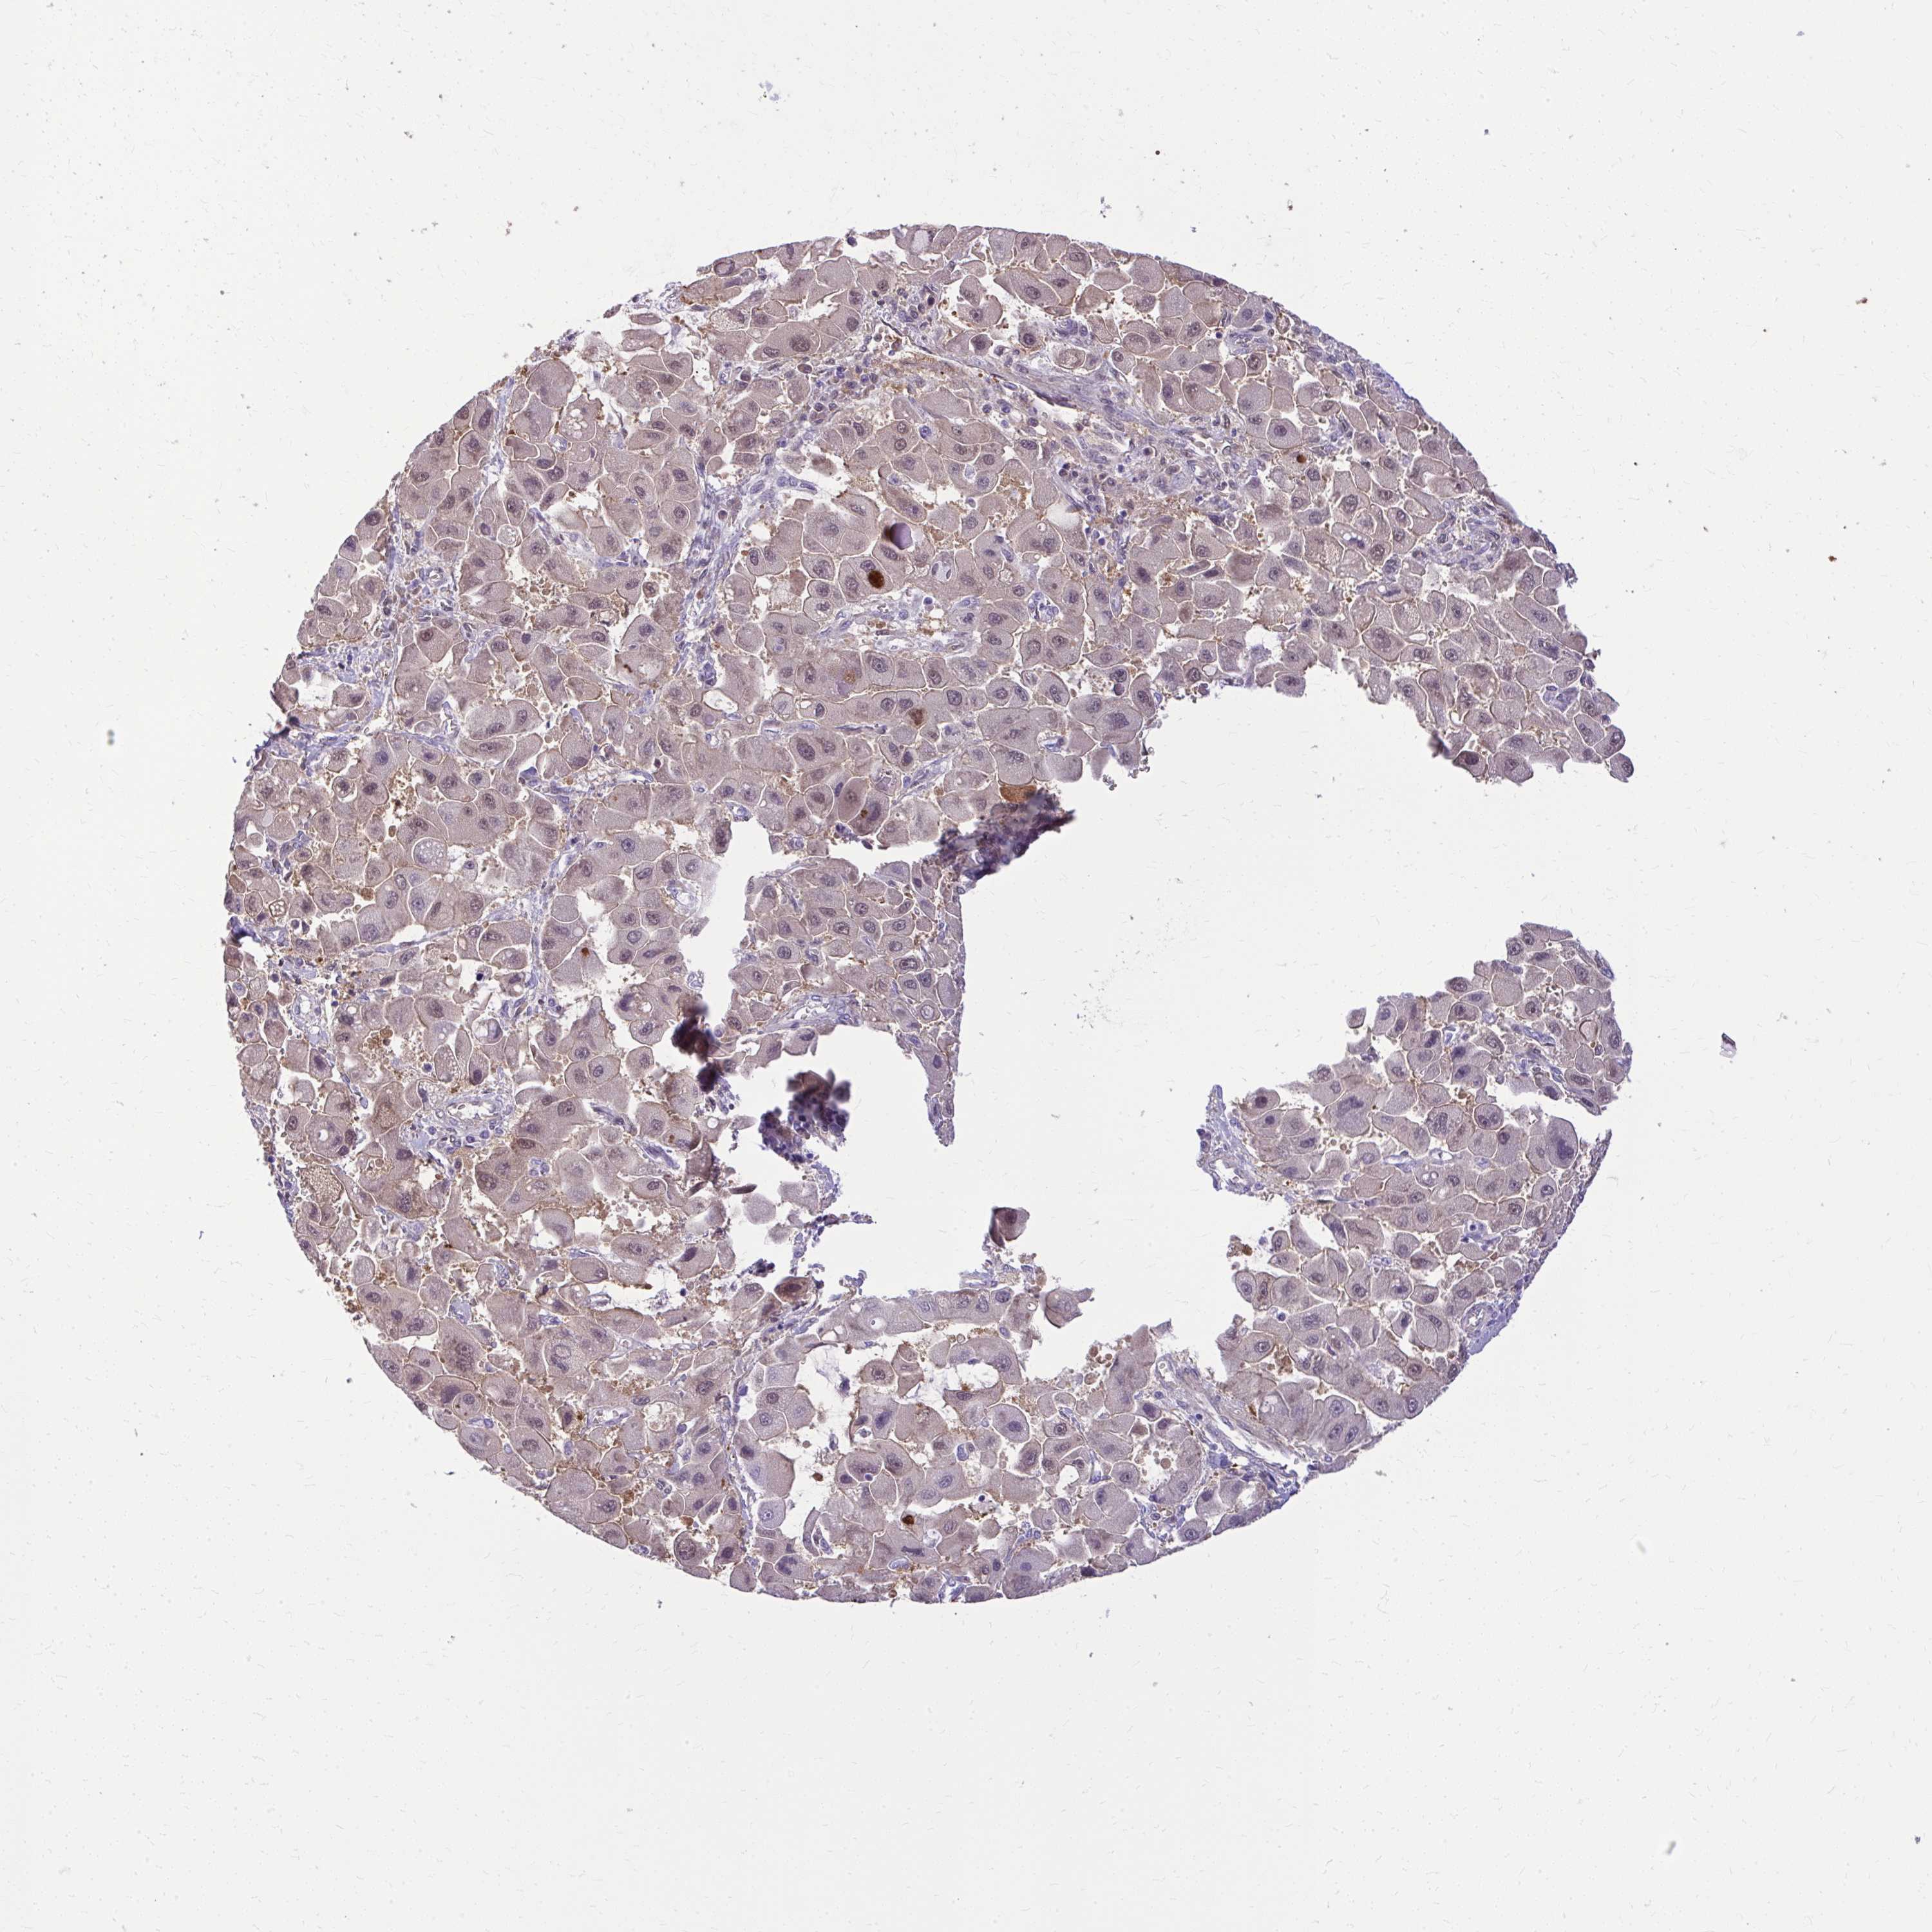

LIVER CANCER - Protein expressioni

A mouse-over function shows sample information and annotation data. Click on an image to view it in a full screen mode. Samples can be filtered based on level of antibody staining by selecting one or several of the following categories: high, medium, low and not detected. The assay and annotation is described here.

Note that samples used for immunohistochemistry by the Human Protein Atlas do not correspond to samples in the TCGA dataset.

Antibody stainingi

Antibody staining in the annotated cell types in the current human tissue is reported as not detected, low, medium, or high, based on conventional immunohistochemistry profiling in selected tissues. This score is based on the combination of the staining intensity and fraction of stained cells.

Each image is clickable and will lead to virtual microscopy that enables deeper exploration of all samples and also displays staining intensity scores, fraction scores and subcellular localization as well as patient and tissue information for each sample.

Antibody HPA059180

Staining

High

Medium

Low

Not detected

Intensity

Strong

Moderate

Weak

Negative

Quantity

>75%

75%-25%

<25%

None

Location

Nuclear

Cytoplasmic/membranous

Cytoplasmic/membranous,nuclear

Carcinoma, Hepatocellular, NOS

Cholangiocarcinoma